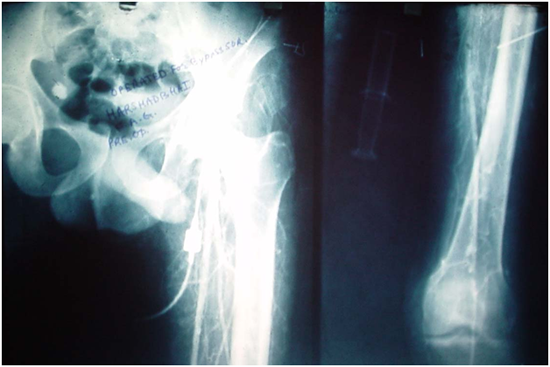

A 25 years old male, heavy smoker and tobacco chewer presented with TAO of left lower limb with non healing ulcer over medial aspect of foot with amputated great, second and third toes. Initially he was treated by general surgeon for lumbar sympethectomy without any improvement. After that vascular surgeon did by pass surgery by putting left radial arterial graft without any improvement. Ultimately patient came to us with rest pain, non healing ulcer with shaggy necrotic tissue.

On arteriogram lower femoral and upper popliteal filling was present with absent dorsalis pedis and posterior tibial.

After failure of conventional methods we took this patient for lateral distraction of spitted tibia for neo histogenesis.